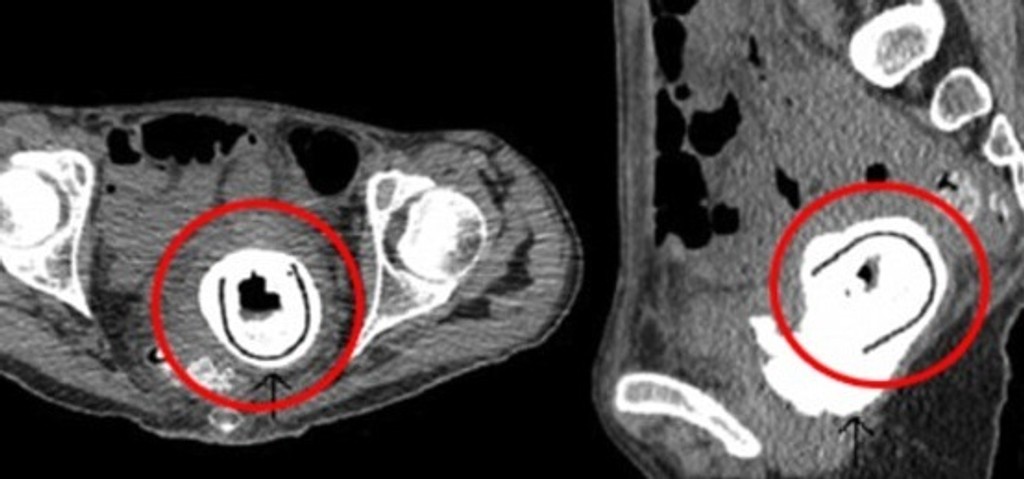

Chirurgovia našli takmer 13-centimetrovú sexuálnu hračku v ženskej pošve. Mala ju tam celých 10 rokov.

Netušila však, čo jej mohlo spôsobiť takéto ťažkosti. Lekári ju po potrebných vyšetreniach poslali na röntgen. To, čo tam videli, ich zarazilo. Žena mala celých desať rokov v maternici sexuálnu hračku. Priznala, že si nepamätá, ako sa tam hračka dostala. Je však podľa nej možné, že ju používala pod vplyvom alkoholu.

Hračka jej ohrozovala život. Mohla spôsobiť vnútorné poranenia, ktoré by mali vážne následky. Jeden čas žena trpela odtokom moču do pošvy a mala obštrukčnú uropatiu.